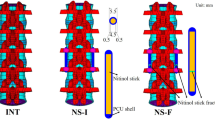

Tensile failure was not observed in our tests as the failure occurred at the screw–tether junction due to complex loads generated by the gripping mechanism of the screw, which was followed by the slippage of the tether. The reason for slippage was observed to be the decrease in the cross-sectional area of the tether caused by the local damage at the screw–tether junction. Failure modes of the tether samples under tensile loading are shown in Fig. 3. The same failure mechanism was observed in all five samples. The failure occurred at the cranial screw–tether junction for three of the samples, whereas two of them failed at the caudal screw–tether junction.